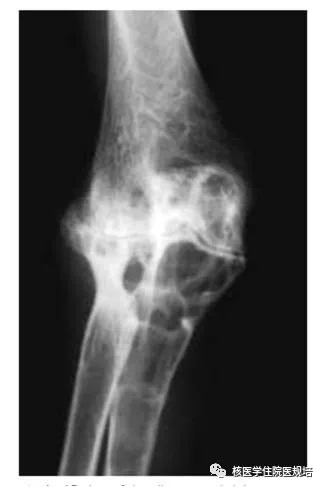

右膝关节平片:诸骨明显骨质增生,关节面硬化,密度不均,关节间隙明显狭窄近消失(图1)。

图1.